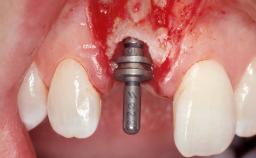

Late Flapless Placement of an Implant in a Maxillary Left Central Incisor Site

A 39-year-old male patient presented with a chief complaint of discomfort and gingival discoloration around his maxillary left central incisor. He was in good general health and was a non-smoker. His past dental history was significant because of the traumatic fracture of tooth 21 in a sporting accident at age 13. Initial dental treatment included endodontic therapy and a full-coverage restoration. The patient became symptomatic 5 years later, when structural failure of the tooth resulted in the dislodgment of the crown. Endodontic retreatment, apical surgery, and post-and-core restoration were performed.

Bone Augmentation Horizontal|Staged

Bone Volume Deficient horizontally, requiring prior grafting